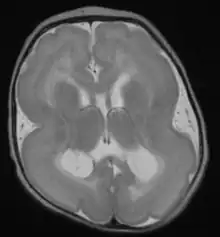

Cobblestone lissencephaly is named after the pebbled or cobblestone appearance of the cortical surface. This uneven cortical surface is due to incomplete organogenesis which leads to no distinguishable layers in the cerebral cortex. Cobblestone lissencephaly shows a reduction and abnormalities in the grey matter of the cerebral cortex.[5]

Different systems for classifying lissencephaly exist. One major distinction is "classic" (type I) vs. "cobblestone" (type II),[23] but some systems add additional forms that fit into neither of these categories.

| Cobblestone (or Type 2) lissencephaly |